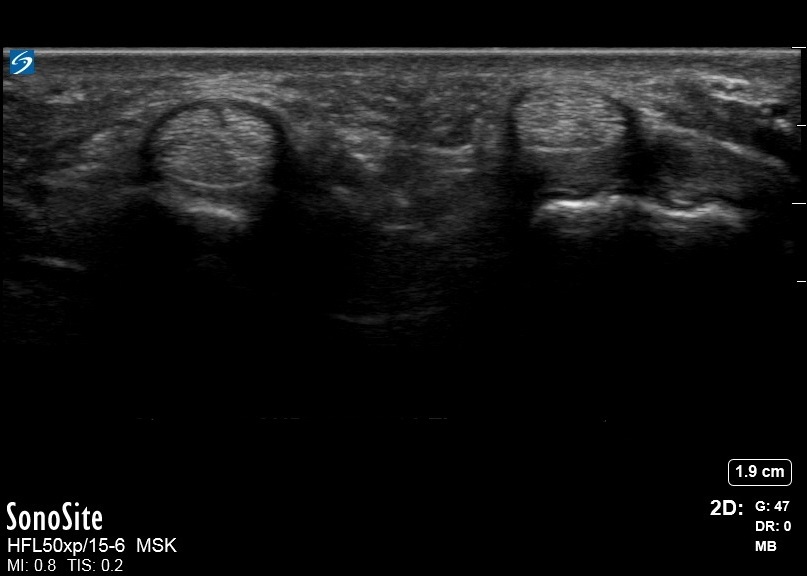

手の正常なA1プーリー画像